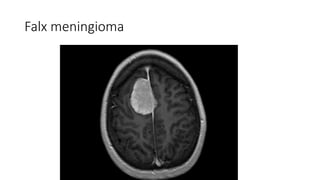

Falx meningioma